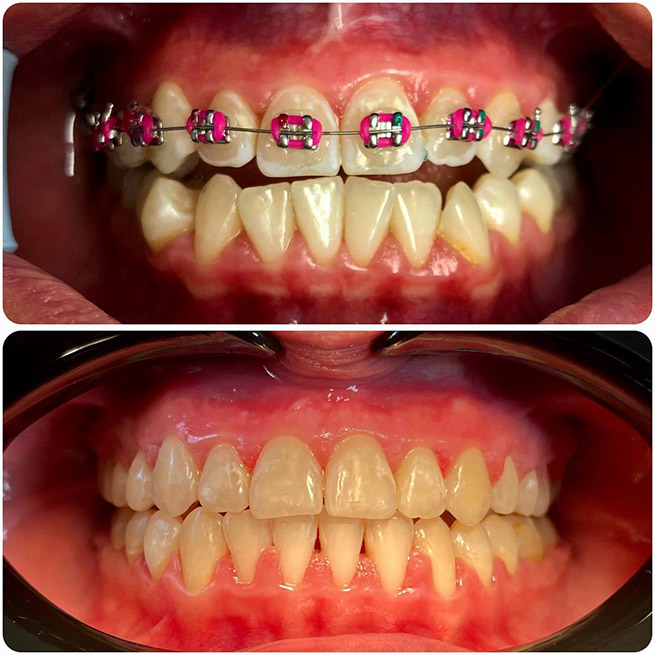

Брекет-системи – класичне та ефективне рішення для виправлення прикусу та вирівнювання зубів. Я працюю з:

- Металевими брекетами (надійні та доступні);

- Самолігуючими брекетами (металеві та керамічні);